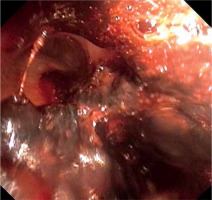

Urgent bronchofibroscopy was performed through a tracheostomy tube and a large clot around the bifurcation of the trachea impairing the patency of both main bronchi was found (Figure 1). Several attempts were made to aspirate the clot with the suction channel of the bronchofibroscope, followed by the use of endoscopic forceps, and by using external suction on the tracheostomy tube (Figure 2). Re-inspection of the airways revealed a severely hyperaemic and oozing area of the mucosa around the bifurcation of the trachea (Figure 3). Due to the extensive mucosal damage, repeated rinsing of the airways several times with norepinephrine solution (4 mg in 250 mL of cold saline) was done and resulted in the resolution of bleeding. Laboratory tests showed no abnormalities in the number of platelets and coagulogram (aPTT, PT, fibrinogen). Subsequently, the patient received a prophylactic dose of enoxaparin.

On the 13th day, the patient was noted to have decreasing levels of oxygen saturation in the blood and the recurrence of ventilation problems was observed. Bronchofibroscopy confirmed the presence of another clot in the area of the bifurcation of the trachea. Several unsuccessful attempts were made to remove the clot using suction and biopsy forceps. Computed tomography angiography of the chest revealed only the presence of a clot (Figure 4). Another round of unsuccessful attempts to remove the clot was done by using lavage, suctioning through the bronchofibroscope working channel, and biopsy forceps. Due to worsening respiratory acidosis and the need for ventilation with 100% oxygen to maintain adequate oxygenation, an attempt was made to remove the clot with the use of increased suction through the endotracheal tube. The tracheostomy tube was then replaced with an endotracheal tube, where bronchofibroscopy was used to position the tube in direct contact with the clot. After the bronchofibroscope was removed, suction was connected to the endotracheal tube and the clot was slowly pulled out along with the tracheal tube [2].